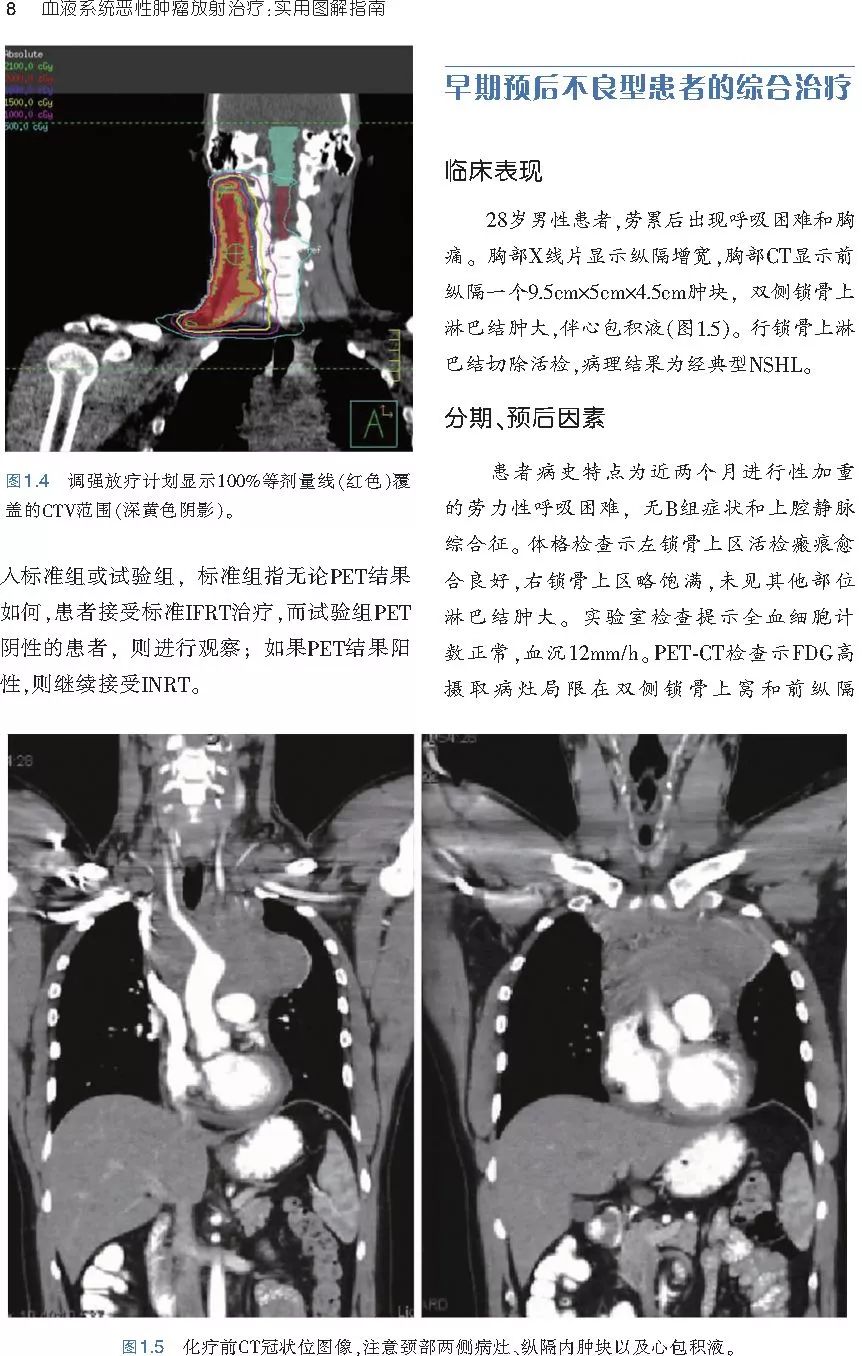

❤ 展开疾病诊断、病理描述及治疗方向的详细阐述,包含医学影像,图文并茂,深入浅出。

本书旨在帮助临床医生对常见血液系统恶性肿瘤疑难病例进行管理,包括霍奇金淋巴瘤、非霍奇金淋巴瘤和白血病患者,并通过多个病例进行阐述。案例讨论遵循标准格式,包括临床描述,其次是与诊断相关的病理描述和分期,然后详细讨论治疗选择。最后,确定治疗方案,并提供所使用的规划放疗技术/方式的图像。对放射肿瘤医生进行临床决策非常有帮助,对于血液病临床医生也有很好的指导作用。